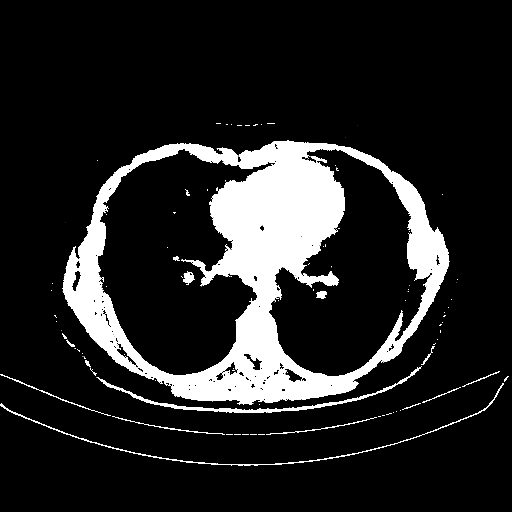

Reconstructed NATIVE CT scan (cycle consistency)

Full window (WL 1023.5, WW 4095 β†’ Low βˆ’1024, High +3071)

Actual HU range: [-1024.0, 3071.0]